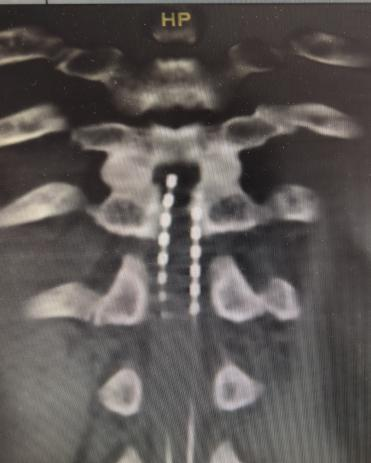

确认测试效果满意后,进行二期手术,植入永久性脊髓电刺激系统。借助测试阶段确定的最佳电极位置,永久电极被精准放置于脊髓相应节段,脉冲发生器埋入腹部皮下。

电极植入位置影像